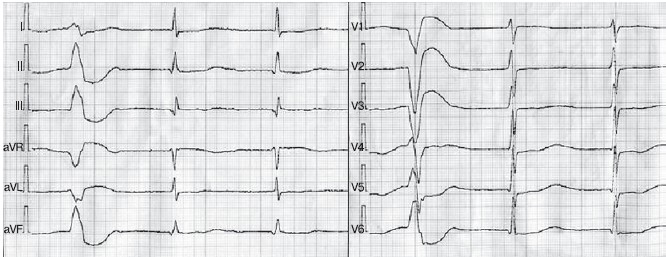

Послеоперационный период протекал тяжело, осложнился развитием длительного пароксизма фибрилляции предсердий, усугублением явлений почечной недостаточности, что обусловливало необходимость 5 сеансов гемодиализа и назначения высоких доз петлевых диуретиков. В течение месяца явления дисфункции почек практически полностью регрессировали. На фоне адекватной инсулинотерапии показатели углеводного обмена находились в удовлетворительном состоянии. Применение амиодарона — антиаритмического препарата III класса в целях профилактики рецидива фибрилляции предсердий оказалось достаточно эффективным, однако повлекло за собой увеличение продолжительности интервала QT на ЭКГ (QT корригированный равен 630 мс) и появление полиморфной желудочковой экстрасистолии (рисунок). К числу факторов риска реализации проаритмогенных эффектов амиодарона у нашей пациентки следует отнести исходный неблагоприятный фон в виде органического поражения сердца, а также развившуюся острую почечную недостаточность единственной почки. На фоне отмены амиодарона, назначения препаратов магния и разрешения явлений острой почечной недостаточности продолжительность интервала QT постепенно нормализовалась и желудочковые аритмии регрессировали. Другим существенным обстоятельством, замедлившим реабилитацию пациентки после операции, оказался тяжелый алкаптонурический артроз тазобедренных и коленных суставов, что является характерным для этих больных осложнением [18]. Следствием длительной вынужденной ограниченности в расширении двигательного режима явилось образование пролежней ягодичной области слева и справа, нижней трети левого предплечья, пяточной области слева, что потребовало активного местного лечения, физической реабилитации, лечебной физкультуры.

Рисунок. ЭКГ пациентки М. от 03.04.2009 г., на которой отчетливо прослеживаются признаки замедления электрической систолы желудочков (продолжительность корригированного интервала QT 630 мс) и частая правожелудочковая экстрасистолия.